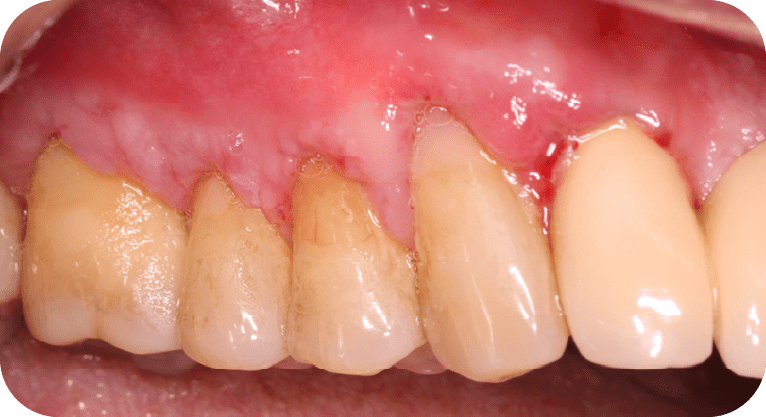

Paciente masculino, “65” años

Tratamiento: Cirugía de encías

El paciente presentaba sensibilidad dental causada por la exposición de los cuellos dentales, por lo que se realizó una cirugía de recubrimiento radicular con injerto gingival y reposicionamiento de encía, logrando

proteger las raíces expuestas, reducir la hipersensibilidad y mejorar tanto la función como la estética periodontal, con resultados satisfactorios para el paciente.

Paciente masculino, “45” años

Tratamiento: Cirugía de encías

El paciente manifestó inconformidad con el aspecto corto de sus dientes, por lo que se realizó una cirugía periodontal de remodelación gingival para recontornear el tejido gingival y exponer mayor superficie dental, logrando así una proporción dentogingival más armónica y mejorando significativamente la estética de su sonrisa.